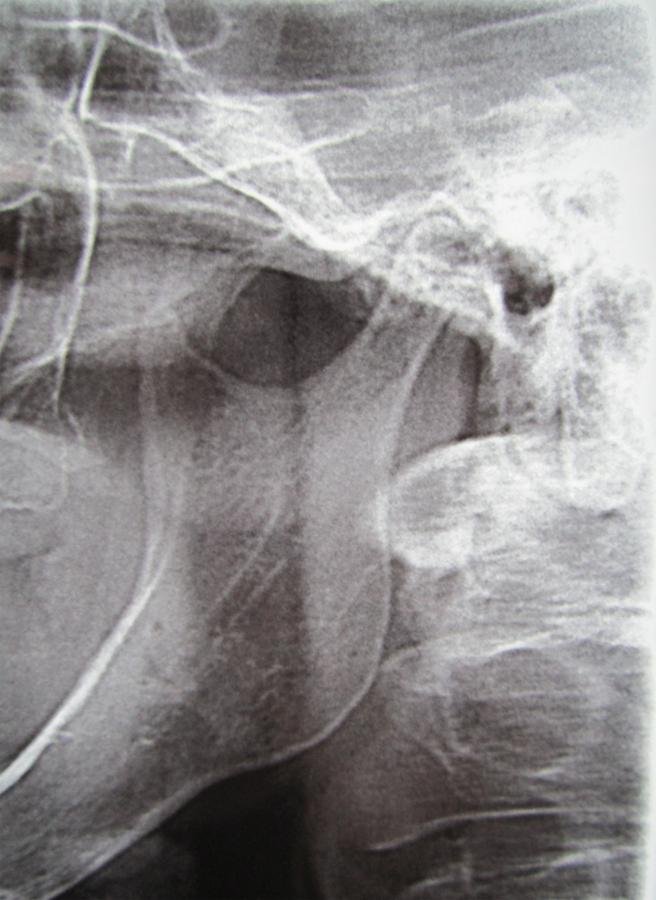

Radiografía panorámica

Julio 5 de 2014

AYUDAS DIAGNÓSTICAS